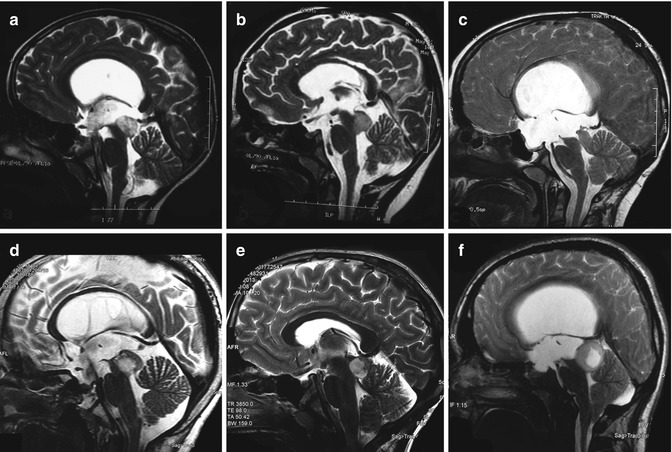

磁共振成像對(duì)頂蓋腫瘤的顯示比CT更可靠,應(yīng)該在每個(gè)患有腦積水的兒童和青少年中進(jìn)行排序。磁共振成像能夠可靠地檢測(cè)到頂蓋腫塊,是一種可靠的隨訪成像方式。對(duì)于腫瘤區(qū)域?qū)Ρ榷仍鰪?qiáng)的重要性,目前還沒(méi)有一致的意見(jiàn)。在18 %的病例中可以看到呈現(xiàn)時(shí)的對(duì)比度增強(qiáng)。據(jù)推測(cè),一開(kāi)始成像的對(duì)比度增強(qiáng)與隨訪期間的腫瘤進(jìn)展之間沒(méi)有相關(guān)性。另一方面,在隨訪期間,全部腫瘤增大的病例都有對(duì)比增強(qiáng)。T2加權(quán)圖像給出了關(guān)于這些病變的更詳細(xì)的解剖信息,特別是腫瘤的生長(zhǎng)方向以及與小腦和被蓋的關(guān)系。

通過(guò)枕部經(jīng)小腦幕和小腦下小腦上入路可以很容易地到達(dá)頂蓋板的病變。

對(duì)于位于該區(qū)域的腫瘤,許多神經(jīng)外科醫(yī)生采用枕部經(jīng)小腦幕入路,以避免可能對(duì)丘的損害。此入路行右枕部開(kāi)顱,并在直竇旁切開(kāi)小腦幕。優(yōu)點(diǎn)是可以直接看到上蚓部、四叉神經(jīng)板和上髓膜之間的裂隙,缺點(diǎn)是可能由于枕葉回縮造成的視力缺陷。同樣的區(qū)域也可以通過(guò)標(biāo)準(zhǔn)的幕下小腦上入路很容易到達(dá),這是一次描述的松果體區(qū)腫瘤。小腦下小腦上入路可用于更靠近尾側(cè)位置的正中位置的、有小腦下入路的腫瘤,以避免眼和聽(tīng)覺(jué)障礙。Ternier等人的以腫瘤體積為中心進(jìn)行決策。小于4立方厘米的腫瘤進(jìn)展的可能性較小(錯(cuò)構(gòu)瘤);體積大于10立方厘米的病變需要考慮早期干預(yù)。在4-10厘米(錯(cuò)構(gòu)瘤或腫瘤)之間的,將受益于頻繁的初始成像。